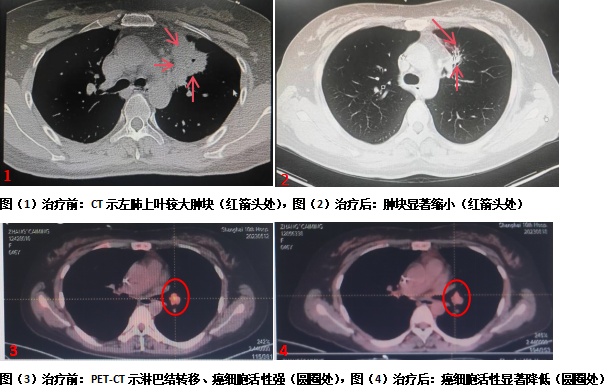

消融治疗在局麻下进行,在CT扫描定位及监测下,将冷冻治疗针精准穿刺置入瘤体,开启冷冻装置后,快速“冻死”了大块癌灶。整个消融治疗过程患者几乎无痛感,消融治疗顺利完成。消融术后,范理宏及其团队为患者张女士制定了白蛋白紫杉醇化疗、免疫药治疗、放疗、抗肿瘤血管生成治疗、新靶点靶向治疗及全程中医药修复线粒体治疗等综合治疗,患者张女士后续的抗肿瘤过程耐受性良好,生活质量较前显著提高。